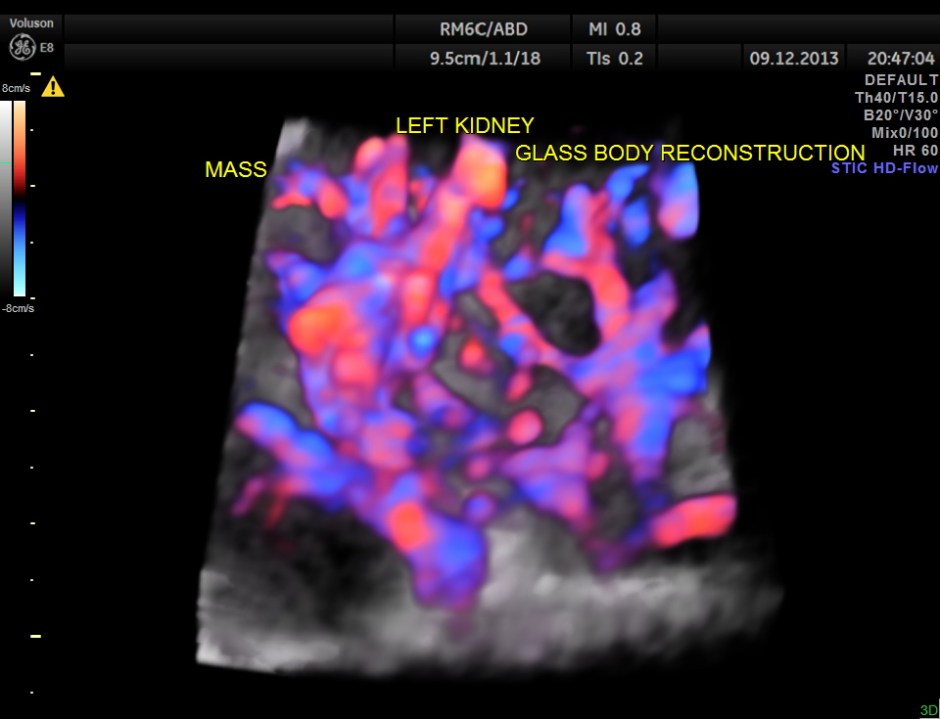

COLOUR FLOW ONLY RECONSTRUCTION.

The findings were confirmed with CT Scan . he underwent radical left nephrectomy and the biopsy was reported as RENAL CELL CARCINOMA.

The images presented above show certain features better seen with reconstruction . But the diagnosis as is usual is made out with the 2 D images .